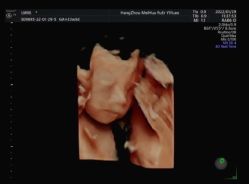

• 杭州贝瑞斯美华妇儿医院·早孕·产检·儿科

• -杭州贝瑞斯美华妇儿医院·早孕·产检·儿科

故事的小黄花 上传于 22-02-07 | 报错